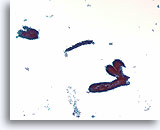

Lobulair carcinoom, Borst FNA, celblok.

Lobulaire carcinoomcellen lijken in het stromaweefsel te zijn ingebed, zodat de indruk wordt gewekt van hypercellulariteit. Dit kan de reden zijn waarom cytologische preparaten van een lobulair carcinoom vaak weinig maligne cellen tonen.

20X

Lobulair carcinoom, Borst FNA, celblok.

Lobulaire carcinoomcellen lijken in het stromaweefsel te zijn ingebed, zodat de indruk wordt gewekt van hypercellulariteit. Dit kan de reden zijn waarom cytologische preparaten van een lobulair carcinoom vaak weinig maligne cellen tonen.

20X

Lobulair carcinoom, Borst FNA, celblok.

Een enkele rij minimaal atypische spaarzame cellen die op en in de stromale fragmenten vastzitten, kan worden waargenomen. Let op de kenmerkende targetoïde intracytoplasmische vacuolen van lobulaire neoplasie.

40X

Lobulair carcinoom, Borst FNA, celblok.

Een enkele rij minimaal atypische spaarzame cellen die op en in de stromale fragmenten vastzitten, kan worden waargenomen. Let op de kenmerkende targetoïde intracytoplasmische vacuolen van lobulaire neoplasie.

40X